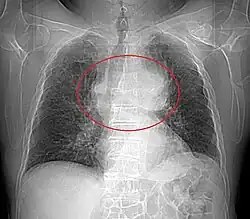

Radiographie thoracique

La radiographie thoracique permet de visualiser entre 45 % et 80 % des tumeurs thymiques[29]. De face, elles présentent un aspect bien délimité, parfois lobulé, débordant d'un côté du médiastin. Le profil permet d'affirmer le caractère rétrosternal de la tumeur, et donc sa localisation dans le médiastin antérieur. Les signes d'envahissement sont rares et peu visibles, et comprennent principalement l'ascension d'une coupole diaphragmatique, faisant suspecter un envahissement du nerf phrénique[28].

Présentation tomodensitométrique classique d'un thymome à un stade précoce (cercle rouge). À l'arrière, l'aorte, la veine cave supérieure et l'artère pulmonaire sont visibles en coupe.